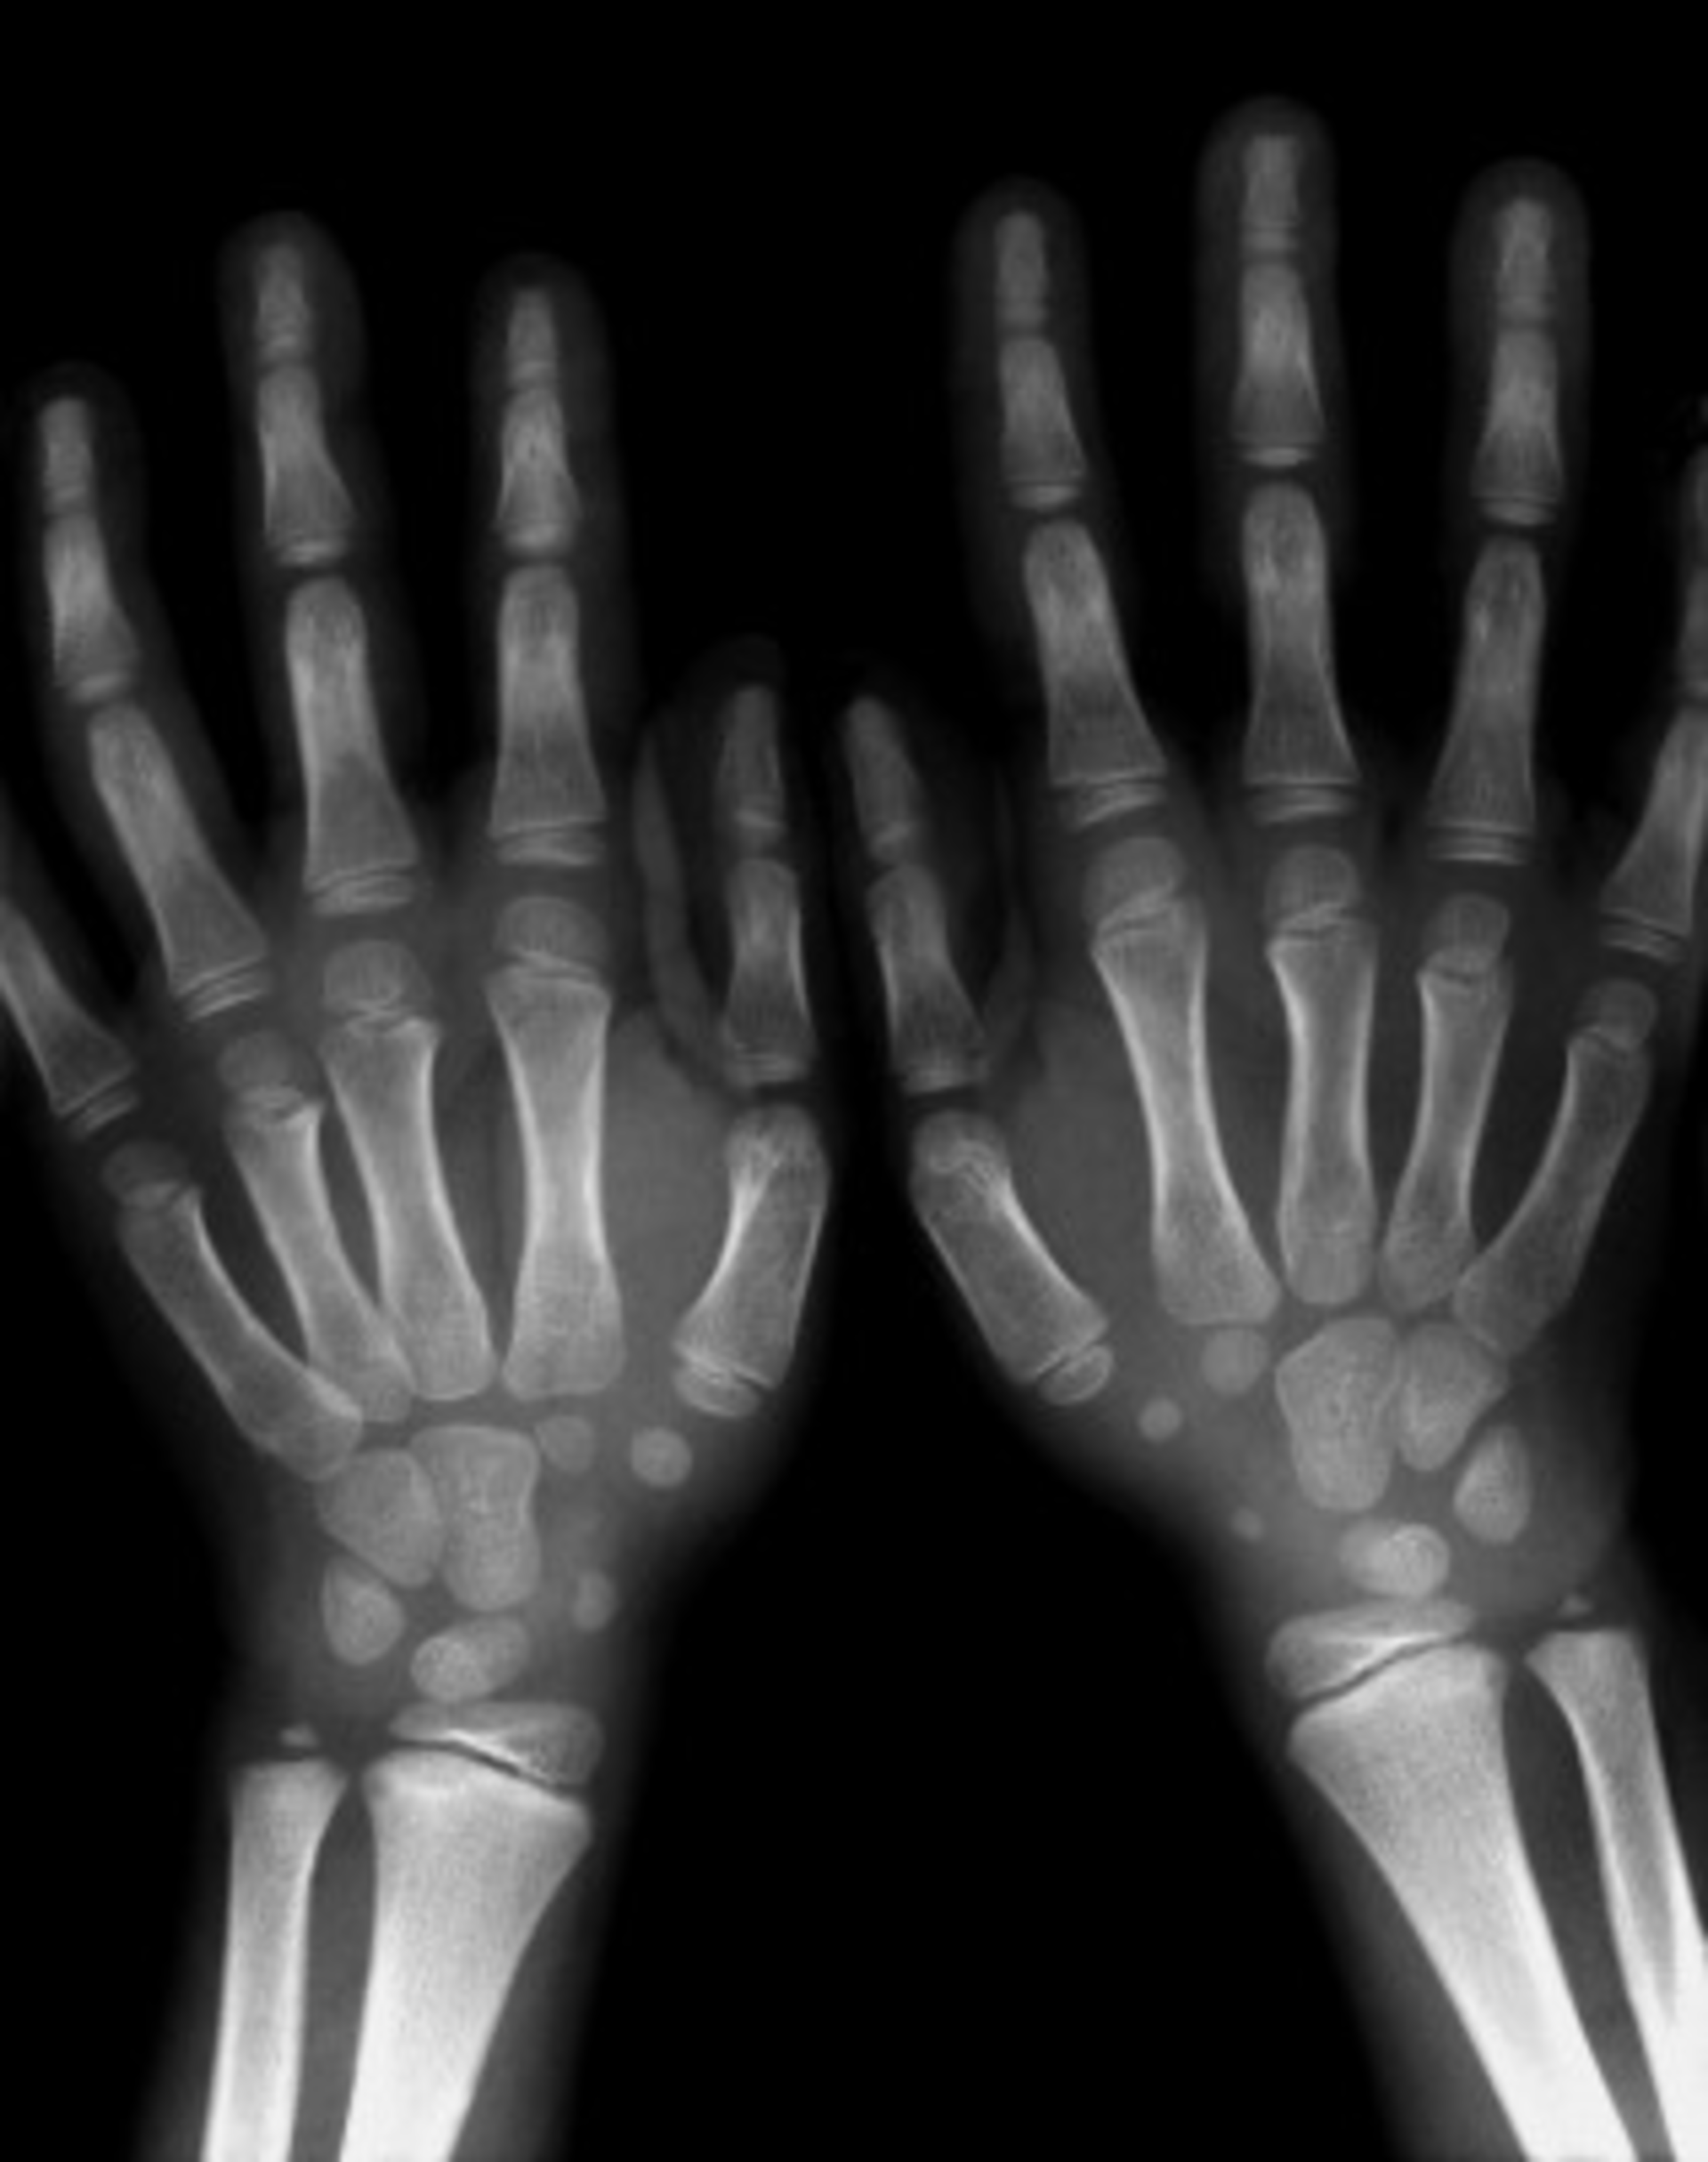

Now that health information exchange (HIE) is gaining traction in the industry and becoming a larger part of meaningful use requirements, researchers at Wake Forest School of Medicine in Winston-Salem, N.C., have been trying to figure out how to make radiological images as mobile as other patient health information. Co-investigators Yaorong Ge, Ph.D., associate professor of biomedical engineering, and Jeff Carr, M.D., radiologist and director, TSI Biomedical Informatics Center, have built the Patient-Controlled Access-key REgistry (PCARE), a set of processes that allows patients, with a swipe of a card, to digitally enable unaffiliated institutions to transfer medical images to avoid the hassle of CDs.

The impetus for developing this technology was to alleviate the bottlenecks of current workflows involved in transferring radiological images between institutions. At many organizations, patients sign paperwork to obtain their radiological images on a CD, which they then have to hand-deliver to the other institution. Often times the patient forgets the CD, or the CD contains the wrong images, or the physician has trouble loading images because of compatibility or hardware issues.